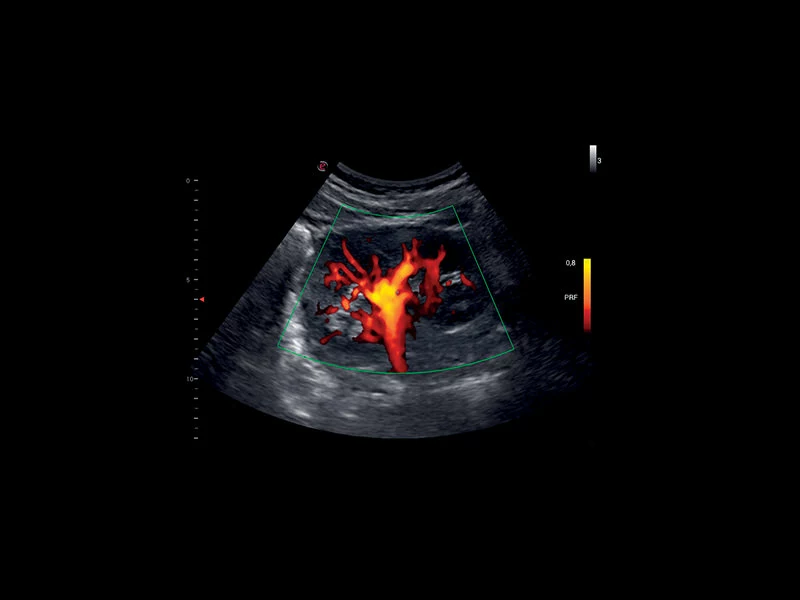

MyLab™9 Platform - XFlow Doppler enhancement in liver vascularization

MyLab™9 Platform - XFlow Doppler enhancement in liver vascularization